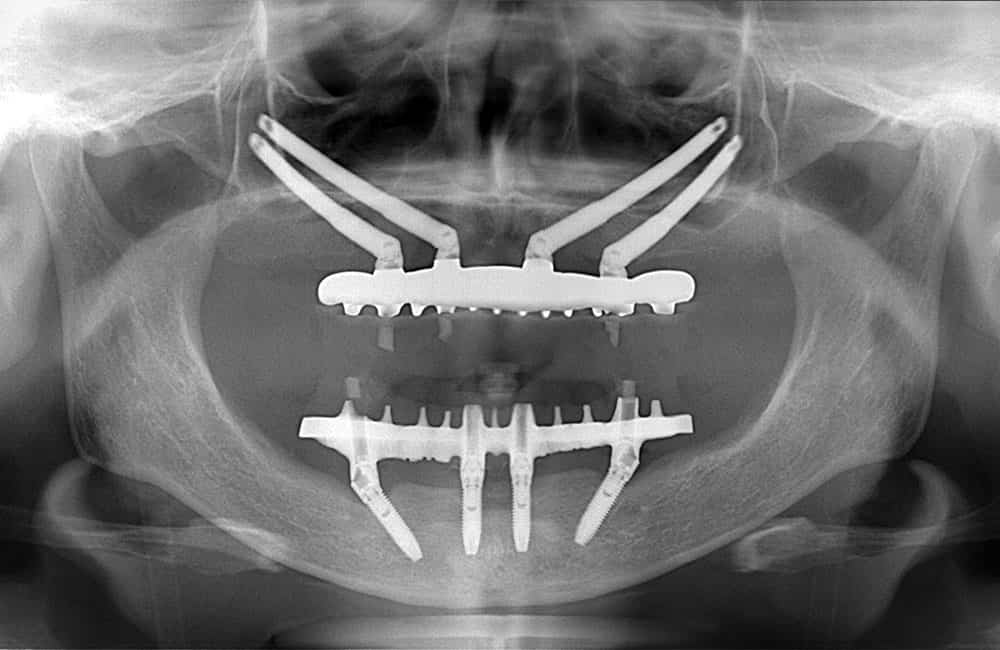

他院でザイゴマインプラント治療を受けた後、仮歯の噛み合わせが悪いため噛みづらく顔貌も変わってしまった。また頬に違和感を感じたため当院を受診。

術前のCT画像

左右のザイゴマインプラントが頬骨から大きく飛び出し頬を触ると違和感がある -

術後のCT画像

前方のインプラントは残し、他院埋入のザイゴマインプラントを除去し、同時に新しいザイゴマインプラントを適切な位置に再埋入を行っております。治療後数年経過しておりますが良好な状態を保っております。